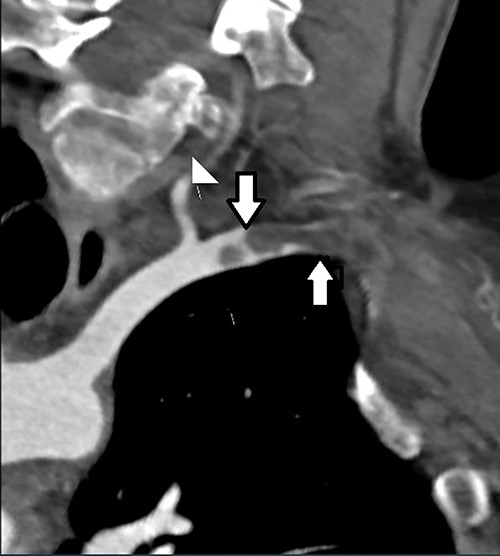

Electrocardiogram showed normal sinus rhythm. The patient’s sudden onset dizziness was investigated with a non-contrast computed tomography (CT) head and was negative for an acute bleed. A CT angiogram of the aortic arch, both common carotids and both upper limbs was performed, which confirmed subclavian artery thrombosis secondary to a left-sided CR and occlusion of subclavian artery, with collateral forearm vessels (Fig. 1).

CT angiogram demonstrating location of the thoracic outlet obstruction (up arrow) and retrograde thrombosis (down arrow).